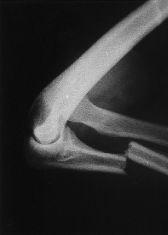

Mecanismo de lesion de esta fractura

Mecanismo INDIRECTO

Caida sobre la mano extendida con el codo en flexion

Se produce por avulsion de una parte de la apofisis por una contraccion del triceps

Tipo de fractura en la clasificacion de Mayo

1a (no desplazada, no conminutada)

Tratamiento de esta fractura

Conservador

Inmovilizar con yeso o ferula a 45-90°, inicio gradural de movilizacion a las 4 semanas